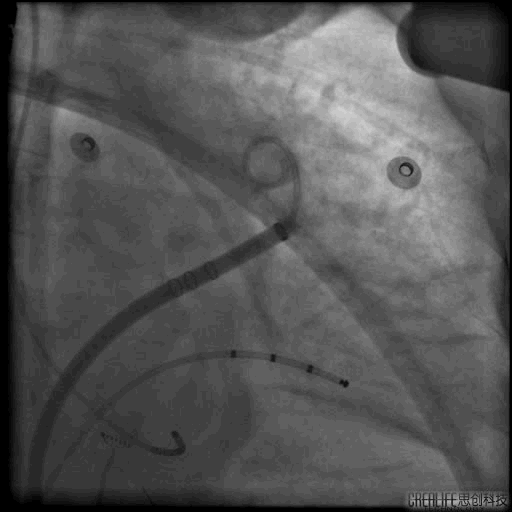

1.房间隔穿刺

房间隔穿刺TEE

RAO30° CAU25°造影,左心耳形态充分暴露,可以观察到心耳属于反鸡翅形状。内部梳状肌较发达,深度较浅。

DSA测量开口17mm,深度19mm,与CT测量结果类似,考虑选择24mm watchman封堵器,首选X3轴向进行封堵。

4. 封堵操作

术中在猪尾导管的保护下,逆时针旋转输送鞘,尽量将输送鞘送入上叶。稳定输送系统,体外预借1mm深度,送入封堵伞,逆时针旋转稳定输送鞘,术中缓慢释放封堵伞。

走上叶缓慢展开后即刻造影观察,无残余分流。压缩比测量12.5%~21%。牵拉测试稳定,符合PASS原则,可以释放。